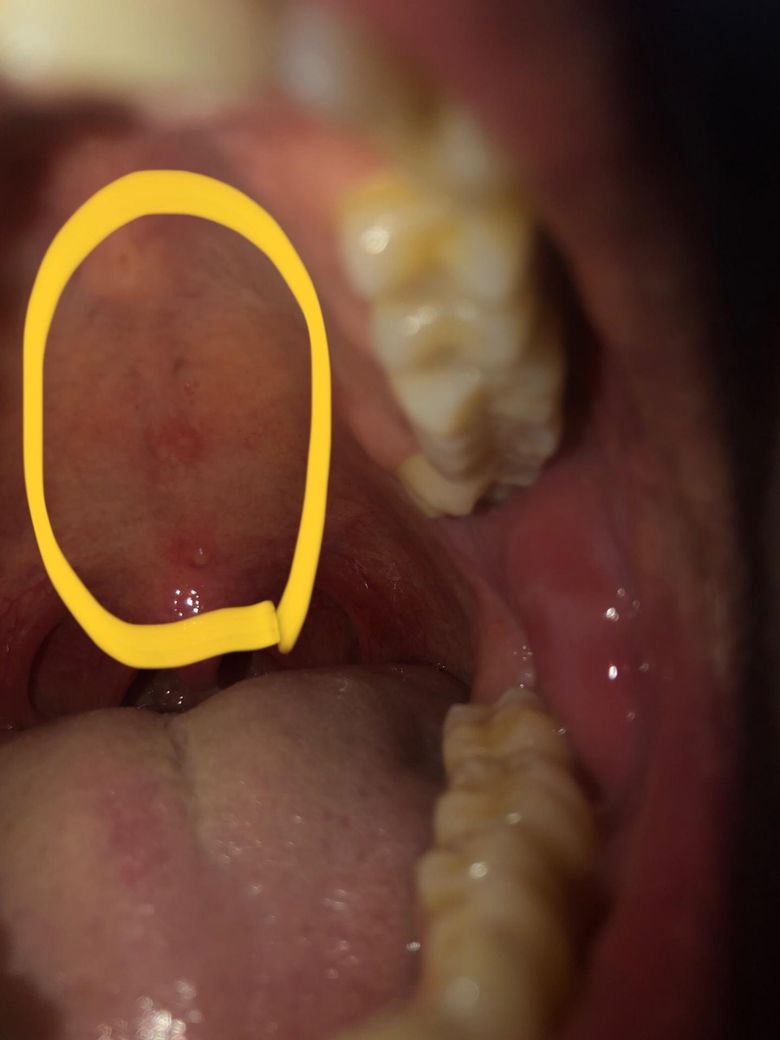

1. 이미지 올렸는데 저기 노란색 부분에서 밑에랑 가운데에 동그랗게 생겼는데 저건 뭔가요? 염증인가요? 저 노란색 부분은 지금 심하게 안부었나요?

1. 골융기로 정상적인 구조물입니다.